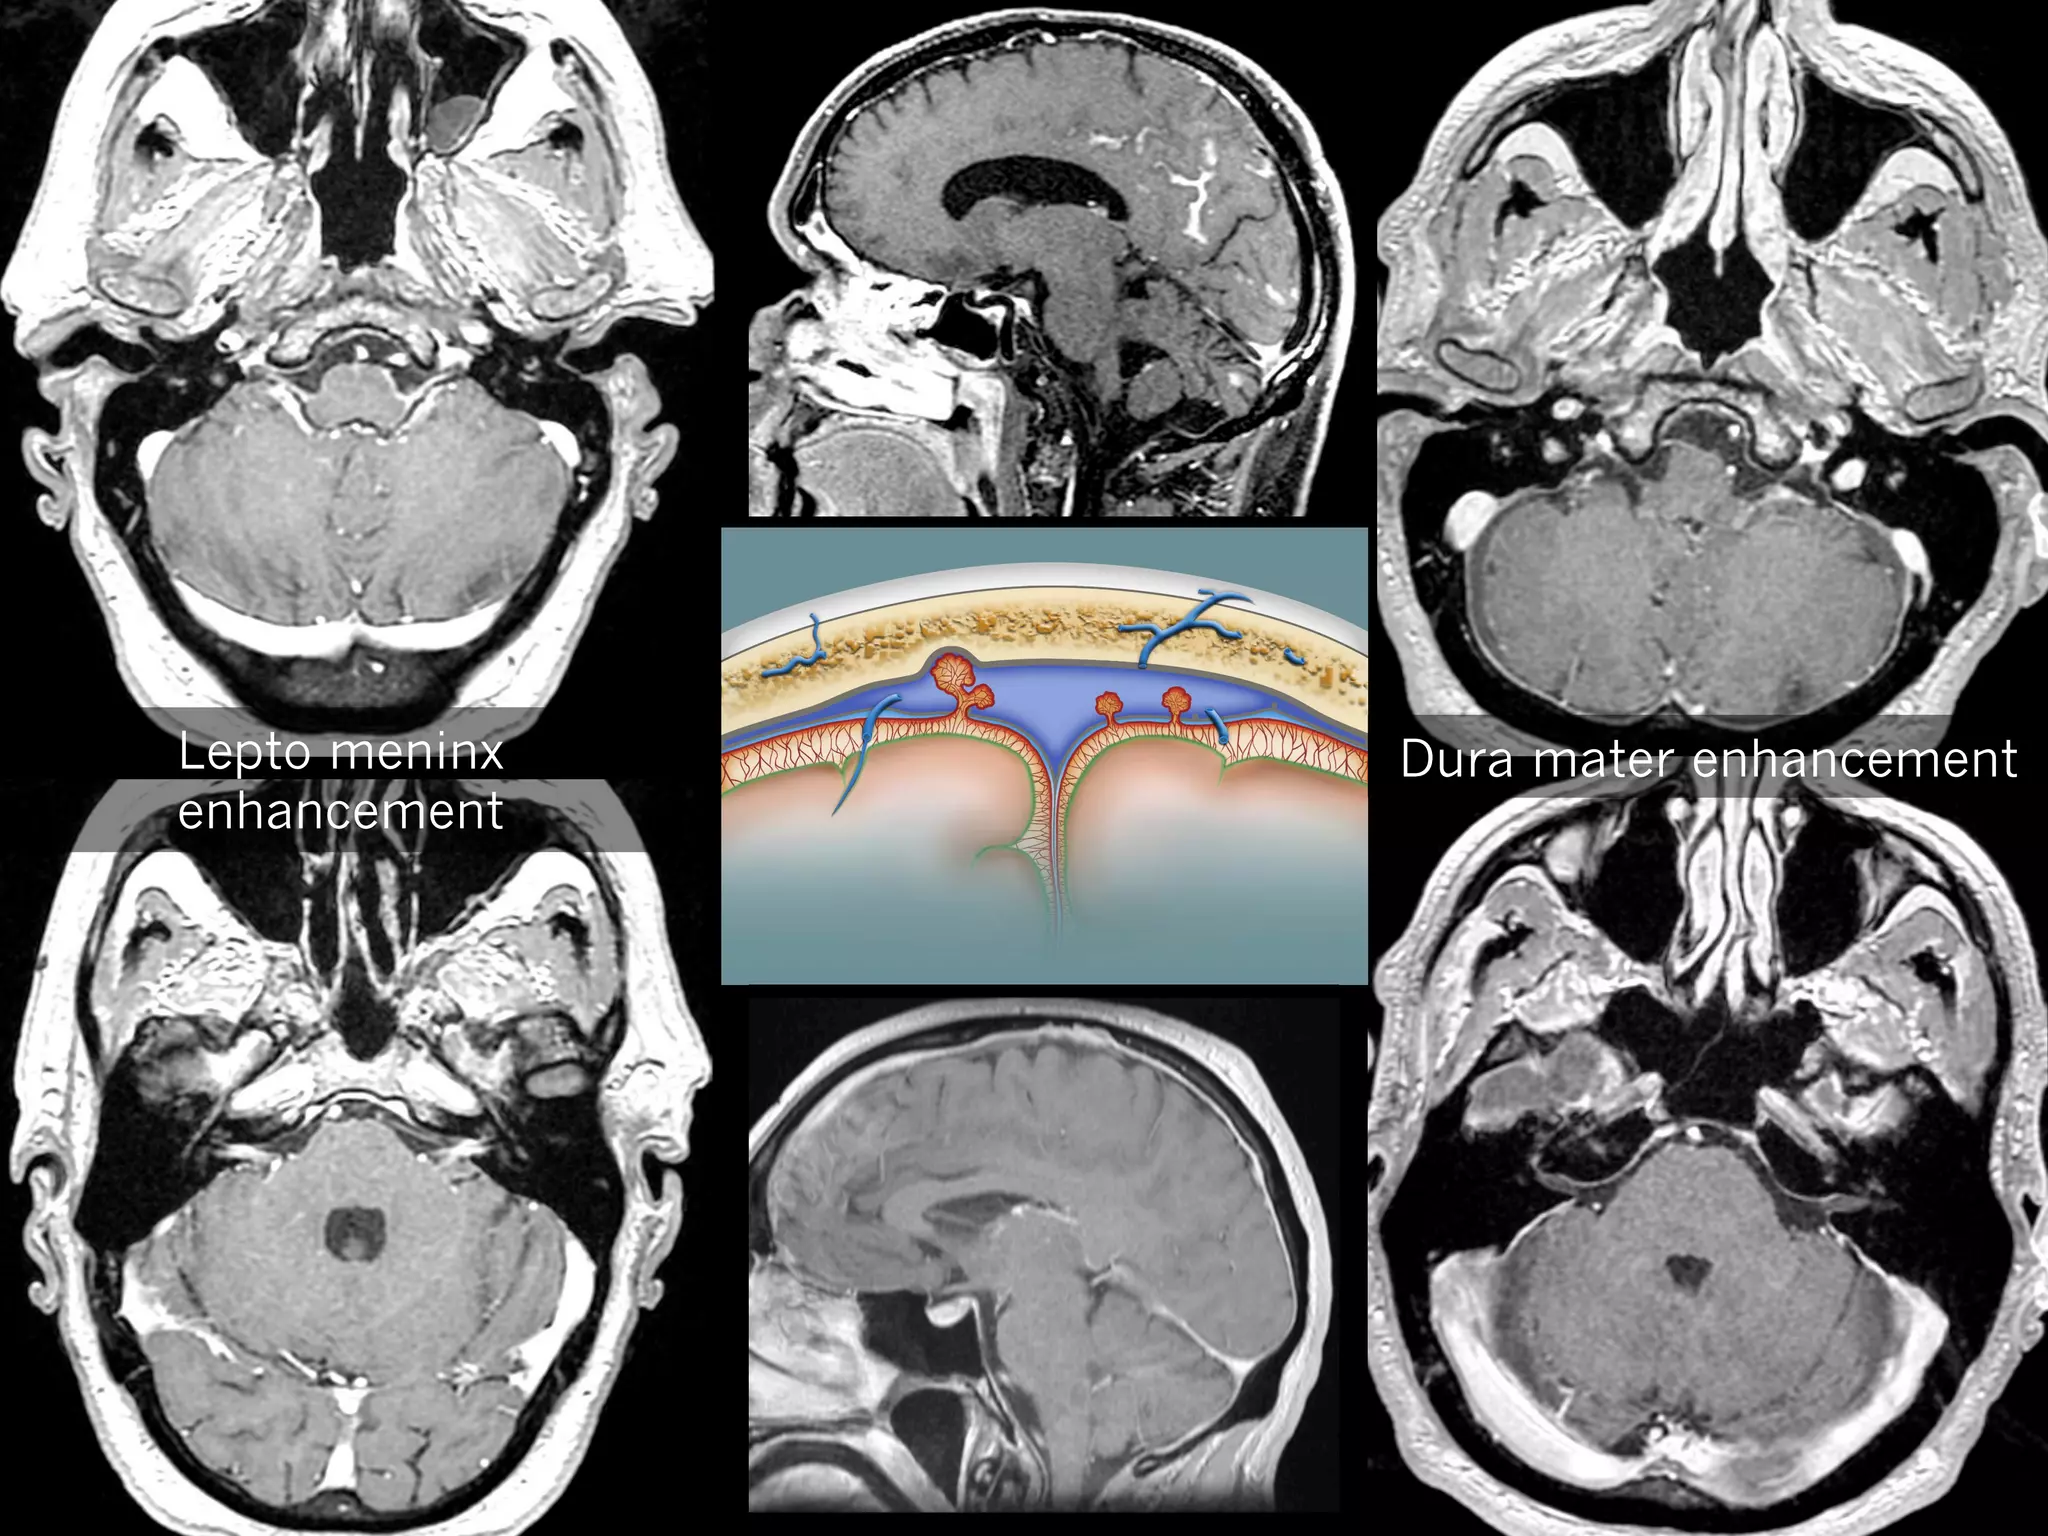

Thickening of dura mater

—  Thickening and enhancement of dura mater, equally

spread, supra and infra tentorial areas

—  Leptomeninges untouched

—  Might be due to dilation of dura mater veins

Lepto meninx

enhancement

Dura mater enhancement

Differential diagnosis

—  Post traumatic

—  Infection

Tuberculosis (leptomeninges are often involved)

—  Inflammation

Sarcoidosis, Wegener’s, PR

—  Tumor

Meningiomatosis, metastasis, lymphoma

Thickening of duramater —  Thickening and enhancement of dura mater, equally spread, supra and infra tentorial areas —  Leptomeninges untouched —  Might be due to dilation of dura mater veins

Differential diagnosis —  Posttraumatic —  Infection Tuberculosis (leptomeninges are often involved) —  Inflammation Sarcoidosis, Wegener’s, PR —  Tumor Meningiomatosis, metastasis, lymphoma